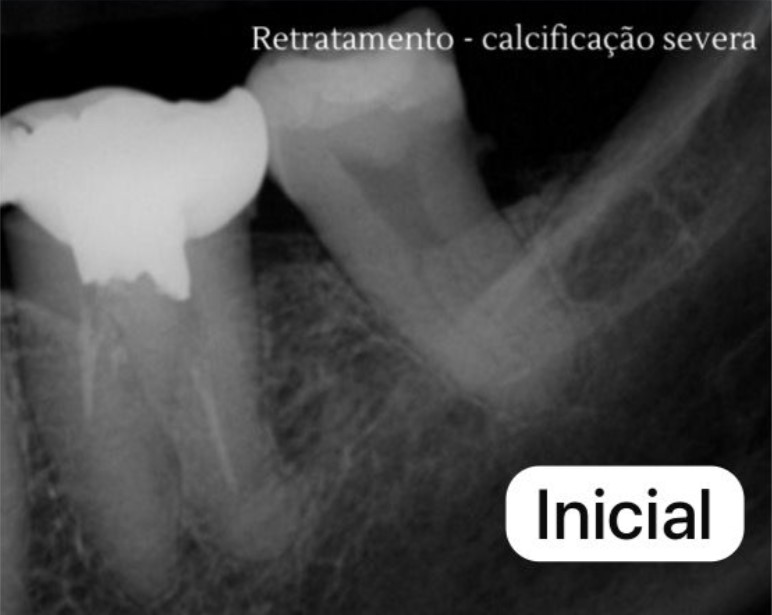

Casos Clínicos

Excelência comprovada em imagens radiográficas.

INICIAL

Diagnóstico Inicial

FINAL

Tratamento Concluído

Detalhes Radiográficos